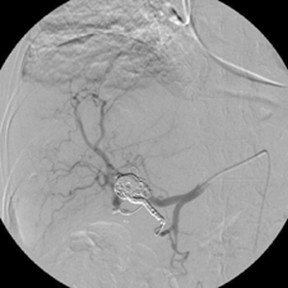

New study @AnnalsofIM bit.ly/2Km3KYu by @DrTalenfeld @WeillCornell: Percutaneous ablation for T1a #renalcancer has similar 5-year survival rates to radical nephrectomy but with far fewer 30-day complications and less #kidneyfailure.